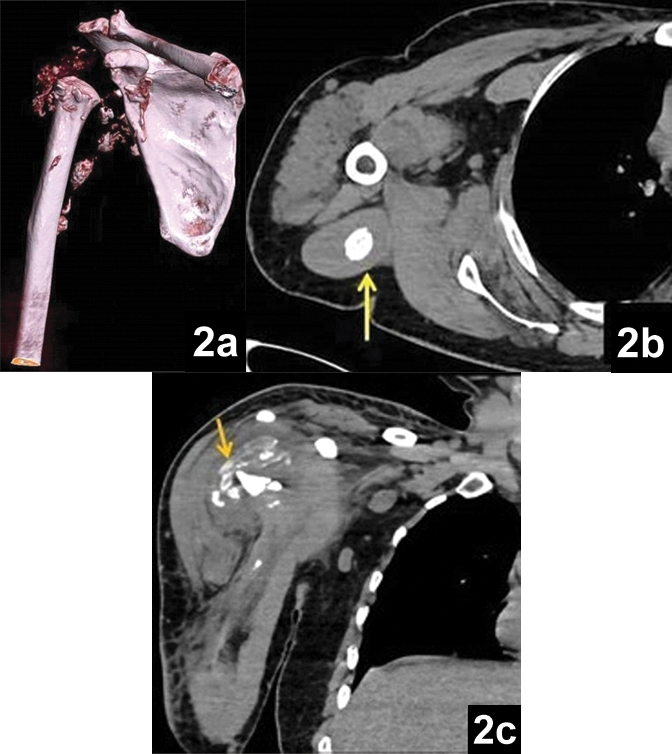

Subsequently, Computed Tomography (CT) and MRI were performed. Unenhanced CT and contrast enhanced MRI showed destruction of head of humerus and glenoid fossa with multiple bony debris within the joint cavity and adjacent muscles with markedly thickened and enhancing synovium and joint effusion [Table/Fig-2,3].

a) Volume rendered image (VRT) showing amputated articular end of humerus and glenoid fossa and multiple periarticular osseous debris; b) Axial soft tissue image showing bony fragment within the triceps muscle (yellow arrow); c) Coronal reformatted image showing fluid collection with multiple osseous fragments within.